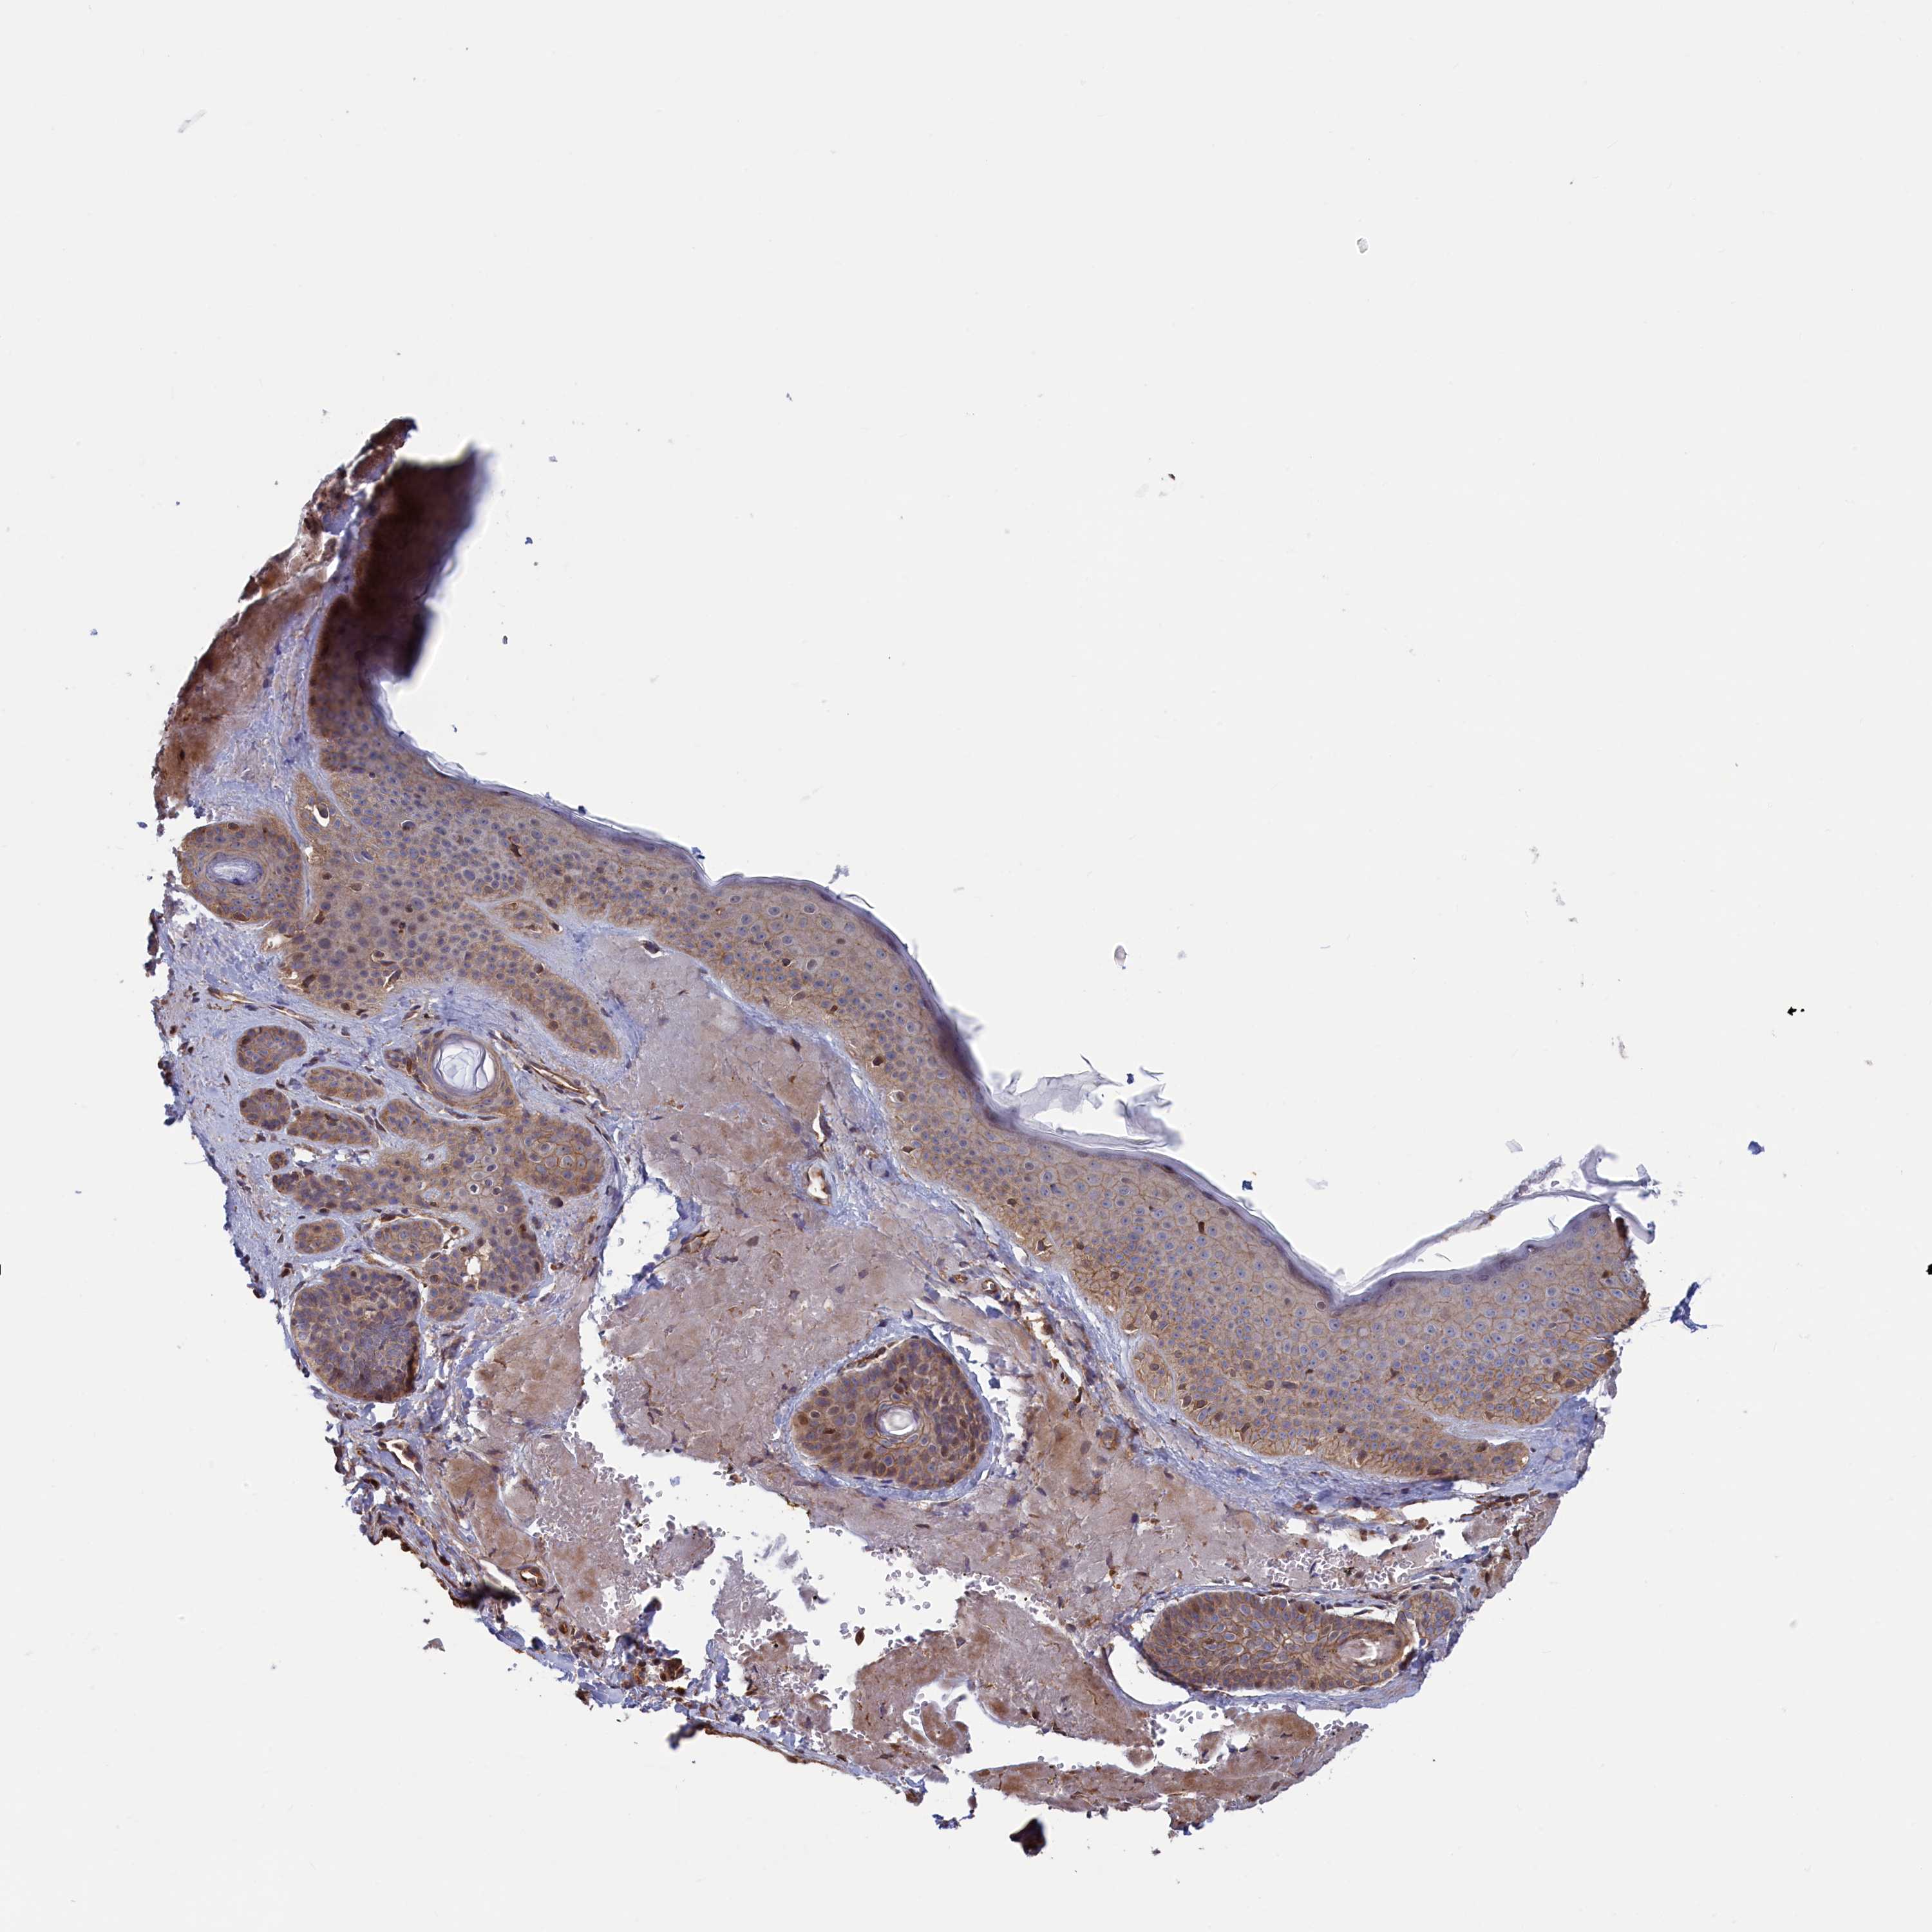

SKIN CANCER - Protein expressioni

A mouse-over function shows sample information and annotation data. Click on an image to view it in a full screen mode. Samples can be filtered based on level of antibody staining by selecting one or several of the following categories: high, medium, low and not detected. The assay and annotation is described here.

Antibody stainingi

Antibody staining in the annotated cell types in the current human tissue is reported as not detected, low, medium, or high, based on conventional immunohistochemistry profiling in selected tissues. This score is based on the combination of the staining intensity and fraction of stained cells.

Each image is clickable and will lead to virtual microscopy that enables deeper exploration of all samples and also displays staining intensity scores, fraction scores and subcellular localization as well as patient and tissue information for each sample.

Antibody HPA041314

Staining

Medium

Intensity

Moderate

Quantity

75%-25%

Location

Cytoplasmic/membranous

Squamous cell carcinoma, metastatic, NOS